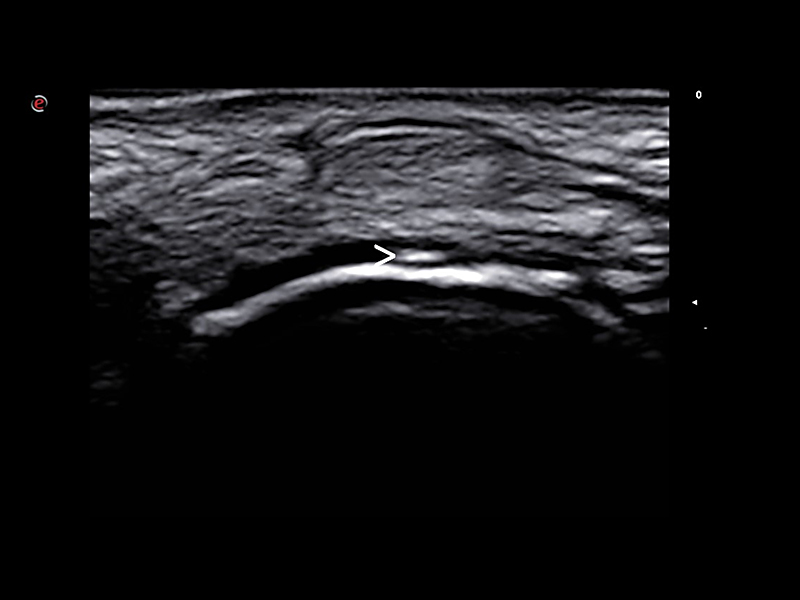

Interventional procedures in rheumatology are used to diagnose and treat conditions affecting bones, joints, muscles, tendons, ligaments, and other related structures. These procedures are often performed under ultrasound imaging guidance to increase accuracy and precision, such as in infiltrations where the brightness of the needle can be emphasized by using Esaote’s advanced Needle Enhancement tool.

Interventional Procedures